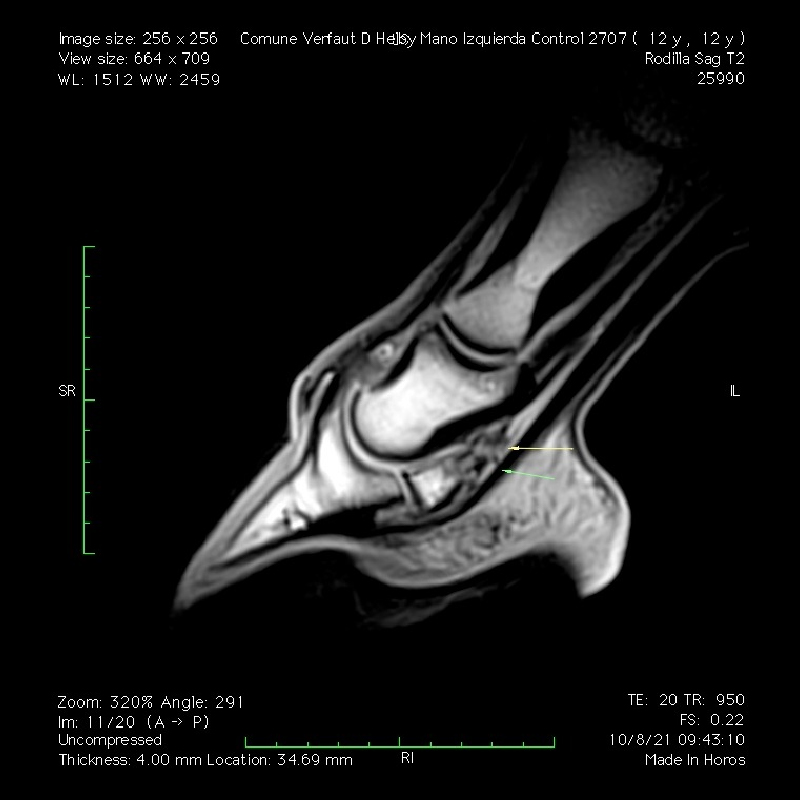

MRI – Resonancia Magnética

0.25 Tesla Esaote Grande Rotating

Estudios con sedación de extremidades anteriores o con anestesia general

Realizamos exploraciones avanzadas que permiten una evaluación profunda de tejidos blandos y estructuras osteoarticulares.

Los principales candidatos para la Resonancia Magnética son caballos que presentan cojeras no localizadas o indetectables mediante radiografía o ecografía, así como casos que requieren un diagnóstico más preciso.

Nuestra tecnología es ideal para el estudio de extremidades, cabeza, primeras vértebras cervicales y casco, y contamos con la única máquina en España capaz de realizar estudios de babilla.